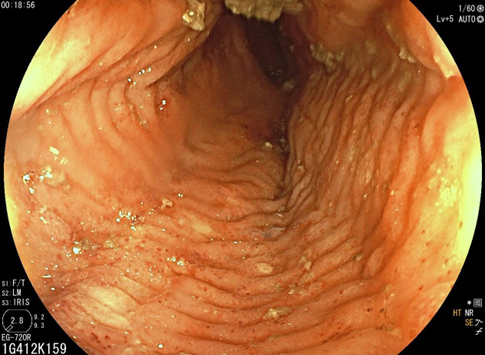

Le pyrosis et le syndrome postural sont des signes typiques de RGO.

Cette symptomatologie épigastrique peut être le reflet d’une gastrite